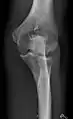

- Knee - AP and Lateral. Intra Condular projections on request

- Patella - Skyline projection

Right knee, anteroposterior

Right knee, lateral

Patella, (slightly skew) skyline